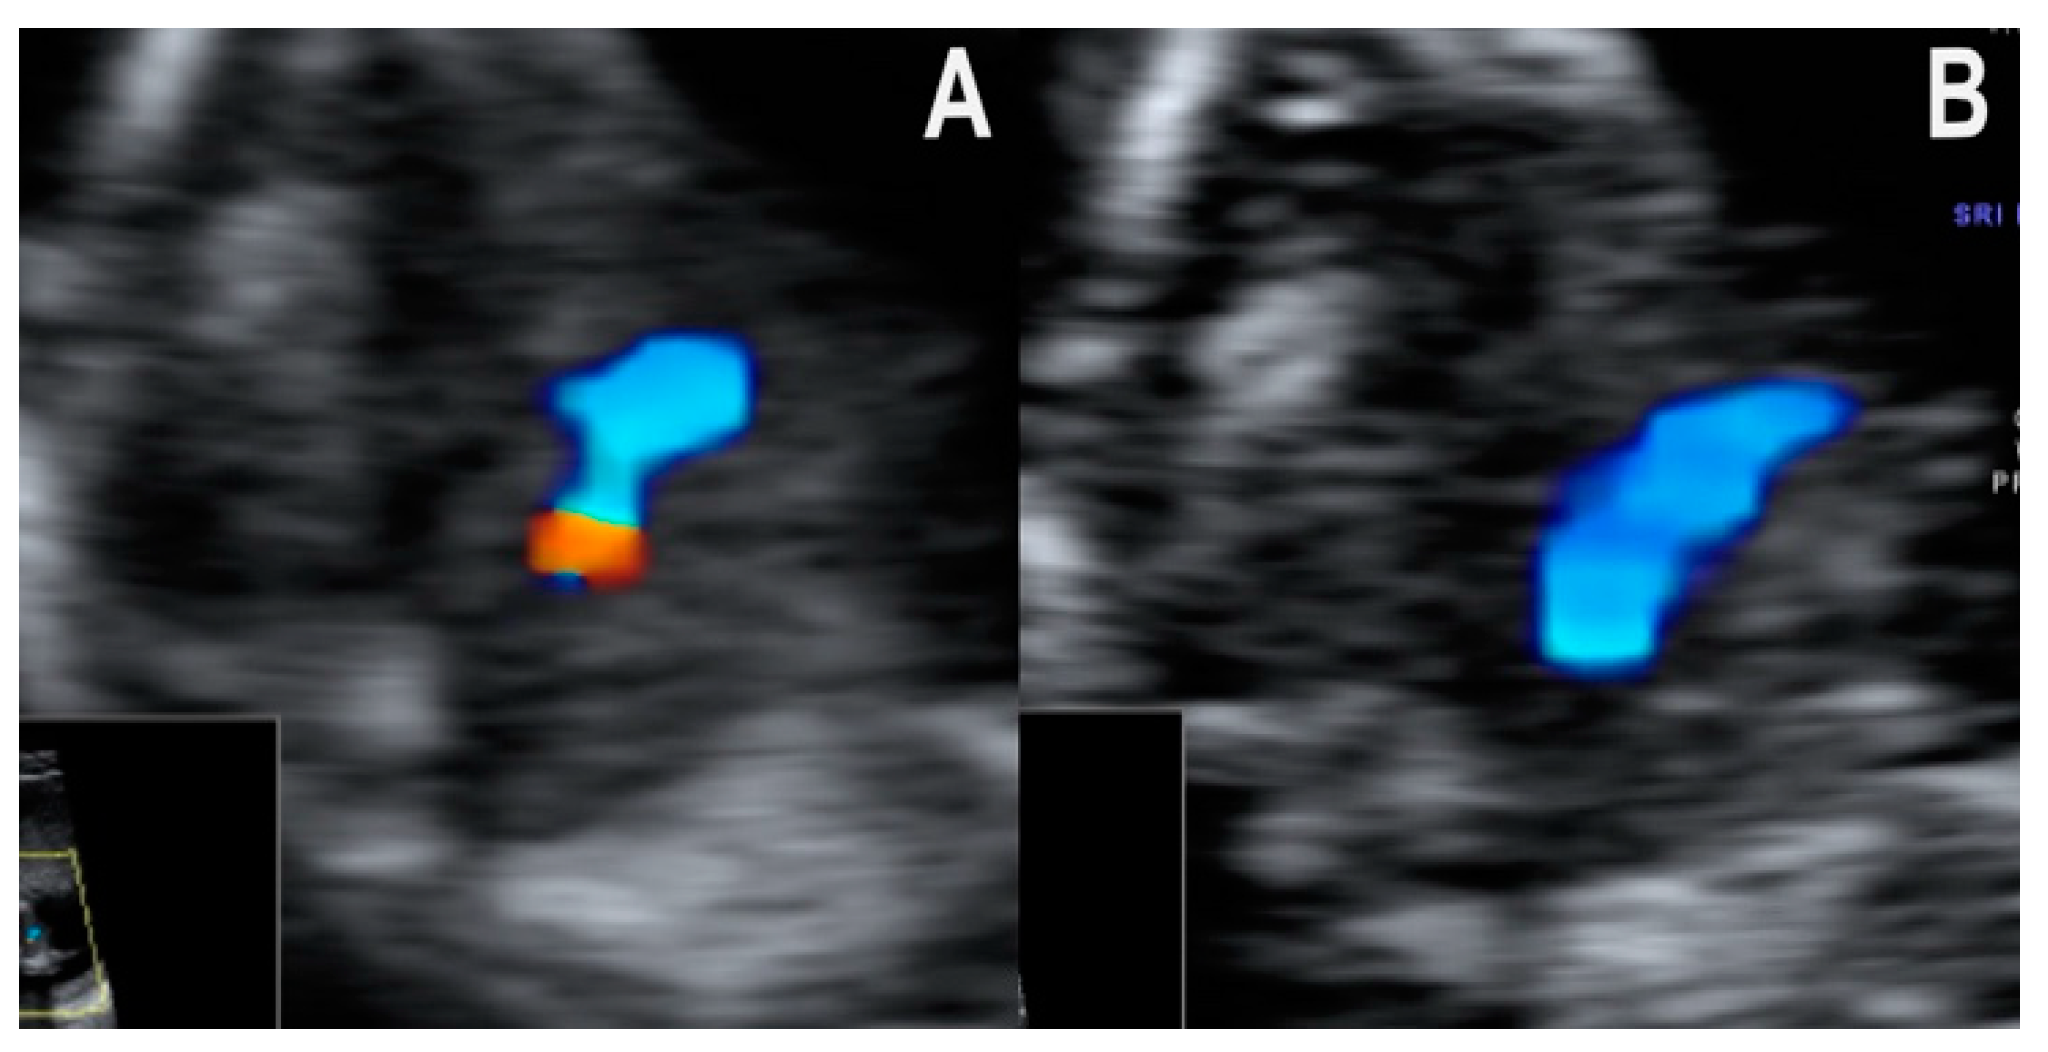

- Normal diastolic filling of both ventricles with an abnormal cardiac axis and one mediastinal vessel with a straight course. We found this pattern in the one case of common arterial trunk from our collection. Filling of both ventricles was seen, but the cardiac axis was abnormally rotated to the left in the four-chamber view. At the level of the three-vessel and trachea view, one big central vessel that seemed to give rise to both pulmonary arteries and the aortic arch was seen (Figure 3A,B). Of note, the single vessel had a rather straight course. In cases of the more frequent and better-known conotruncal malformations, TOF and DORV, the dominant vessel is characteristically curved [8], but no clear data on CAT are available. In this case, the diagnosis was confirmed only by second trimester echocardiography performed by a fetal cardiology specialist.